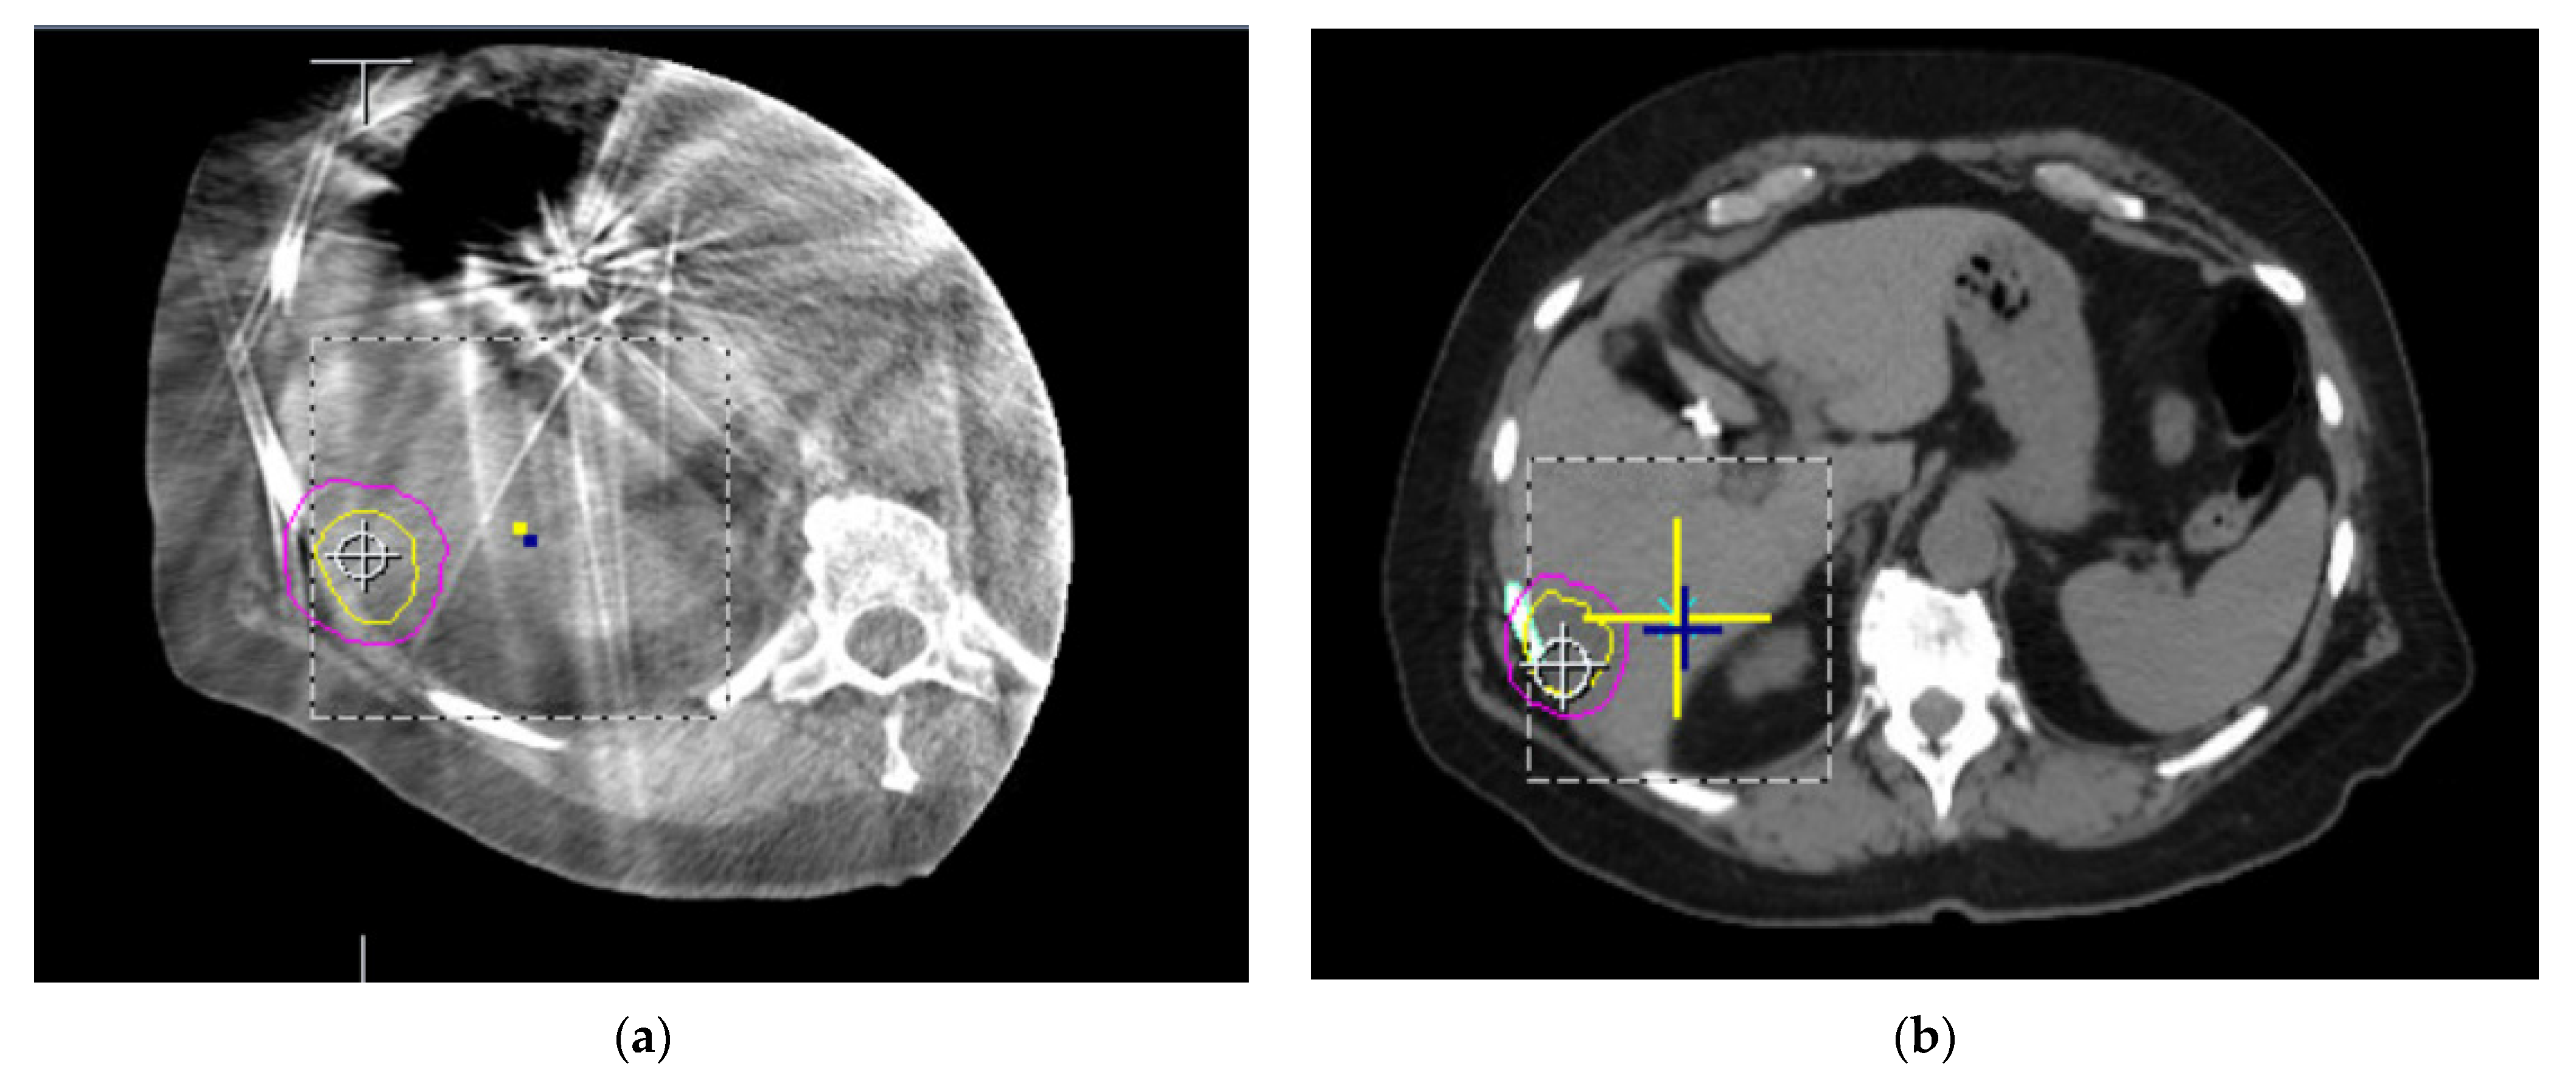

- Kulkarni, N.M.; Hong, T.S.; Kambadakone, A.; Arellano, R.S. CT-guided implantation of intrahepatic fiducial markers for proton beam therapy of liver lesions: Assessment of success rate and complications. AJR Am. J. Roentgenol. 2015, 204, W207–W213. [Google Scholar] [CrossRef]

- Kothary, N.; Heit, J.J.; Louie, J.D.; Kuo, W.T.; Loo, B.W.; Koong, A.; Chang, D.T.; Hovsepian, D.; Sze, D.Y.; Hofmann, L.V. Safety and efficacy of percutaneous fiducial marker implantation for image-guided radiation therapy. J. Vasc. Interv. Radiol. 2009, 20, 235–239. [Google Scholar] [CrossRef]

- Valentine, K.; Cabrera, T.; Roberge, D. Implanting metal fiducials to guide stereotactic liver radiation: McGill experience and review of current devices, techniques and complications. Technol. Cancer Res. Treat. 2014, 13, 253–258. [Google Scholar] [CrossRef]

- Padgett, K.R.; Simpson, G.; Asher, D.; Portelance, L.; Bossart, E.; Dogan, N. Assessment of online adaptive MR-guided stereotactic body radiotherapy of liver cancers. Phys. Med. 2020, 77, 54–63. [Google Scholar] [CrossRef] [PubMed]